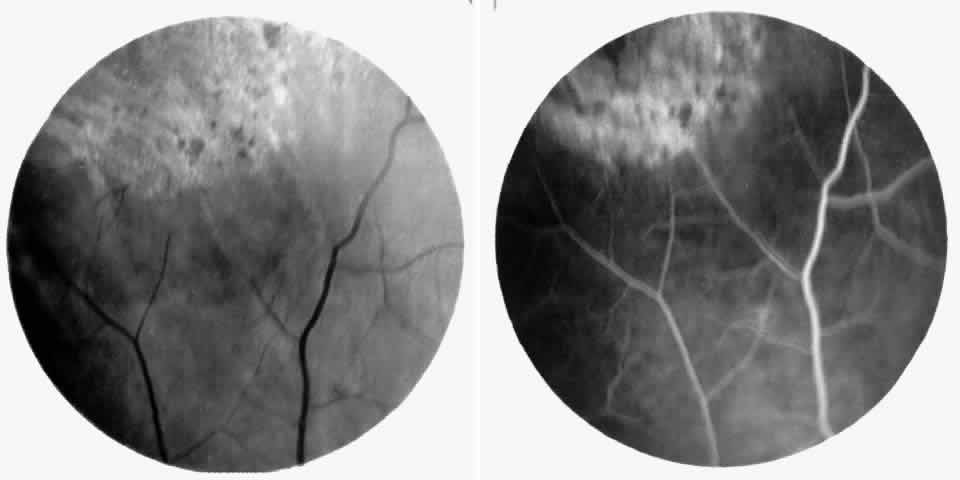

Macular Small Vessel Occlusions

Occlusions of the fine vasculature of the macular and perimacular area have been reported in 10% to 40% of patients with sickle cell disease.18,83,91–99 In the acute phase, the occluded vessel will have a dark red appearance and may appear as a dark line on fluorescein angiography (Fig. 9). Nerve fiber layer infarcts (cotton-wool spots) are seen (see Fig. 8D and E;Fig. 10).100

Fig. 9. A 27-year-old man with homozygous sickle cell anemia. A. Fluorescein angiogram of the right eye shows multiple arteriolar occlusions temporal to the fovea (arrows). B. Same area 6 months later shows more extensive occlusions. The black arrowheads (A and B) identify corresponding arteriolar bifurcation.

Fig. 10. A 33-year-old woman with SC disease and stage III sickle cell retinopathy. A. Photograph of the right eye shows a cotton-wool spot with a dark segment identifying the occluded vessel (arrow). B. Fluorescein angiogram demonstrates nonfilling of the occluded vessel (arrow). C. Eighteen months later, the occluded vessel is still visible (arrow). D. Fluorescein angiogram demonstrates that there is still nonfilling of the vessel (arrow).